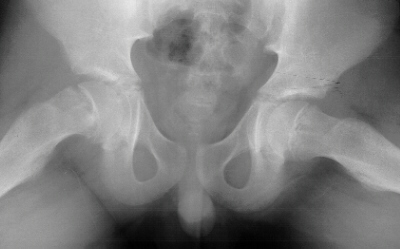

An 11 year old boy presented with a one year history of right knee

pain. He stated that his knee recently "gave way" when running

down the stairs at school. He described his discomfort as a deep achy pain

on the medial aspect of his knee. There was no history of trauma, nor had

the pain limited his activities until recently. The boy denied numbness,

paresthesias or weakness in his right leg. He had no fevers, chills, and

any recent illnesses. Examination revealed an obese adolescent male in

no acute distress. Height is 149cm(50%) Weight is 59 Kg (>95%). The

right knee appeared atraumatic without any areas of point tenderness. There

was diffuse pain in the knee with passive ROM. No effusion was present

in the knee. An xray of the knee was obtained and found to be normal. Hip

x-rays are above.